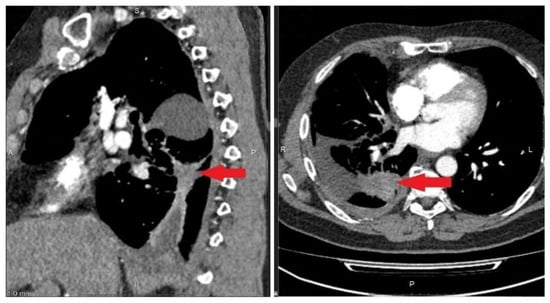

3.6.2. A Clinical Example Demonstrating a Unfavorable Outcome of the Disease and the Evolution of the Number of CTCs Detected in the Peripheral Blood